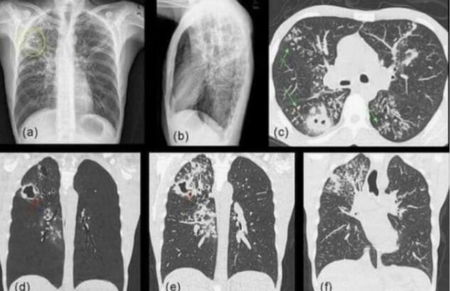

Una delle tante stravaganti teorie che viaggia veloce sui social (senza esser confermata dai medici che, oltretutto, la smentiscono) è quella relativa alla candida polmonare provocata dall’uso delle mascherine. Tra Facebook, Twitter e Whatsapp negli ultimi giorni circola una foto che mostra gli effetti di questa infezioni a livello polmonare. La patologia esiste, ma non c’entra nulla con l’utilizzo dei dispositivi di protezione. Si tratta di un fungo che, per definizione, arriva da fattori esterni.

«Osservate bene, si chiama candida polmonare. È quello che sta succedendo e rilevando dovuta all’eccessivo uso delle mascherine. Ci stanno ammalando un po’ alla volta quando il vaccino sarà obbligatorio molte persone moriranno», si legge in uno dei tanti posti complottisti che circolano in rete. Altri, invece, la descrivono così.

Come riporta Butac, Reuters aveva già smentito questa teoria che circolava fin dal mese di luglio. La verità sulla (non) correlazione tra uso delle mascherine e candida polmonare la fornisce lo pneumologo Thomas Nash: «L’unica cosa che colpisce la maschera è quello che espiriamo noi, ovvero persone che sono in salute non espirano funghi (che causino la candida polmonare)». E invece, come comprensibile facendo una rapidissima ricerca su Google, la candida polmonare è un’infezione micotica provocata da fattori esterni (quindi i famosi funghi). Ricordiamo, inoltre, che se fosse veritiera questa fake news, i medici e chirurghi ‘costretti’ da sempre a indossare la mascherina per molte ore consecutive sarebbero condannati a questo tipo di infezione.